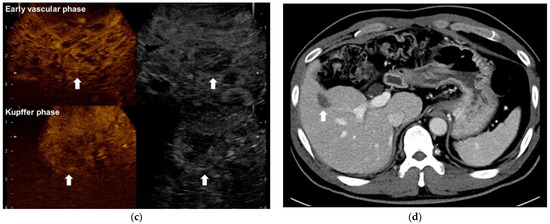

- Park, H.S.; Kim, Y.J.; Yu, M.H.; Jung, S.I.; Jeon, H.J. Real-time contrast-enhanced sonographically guided biopsy or radiofrequency ablation of focal liver lesions using perflurobutane microbubbles (sonazoid): Value of Kupffer-phase imaging. J. Ultrasound Med. 2015, 34, 411–421. [Google Scholar] [CrossRef] [PubMed] [Green Version]